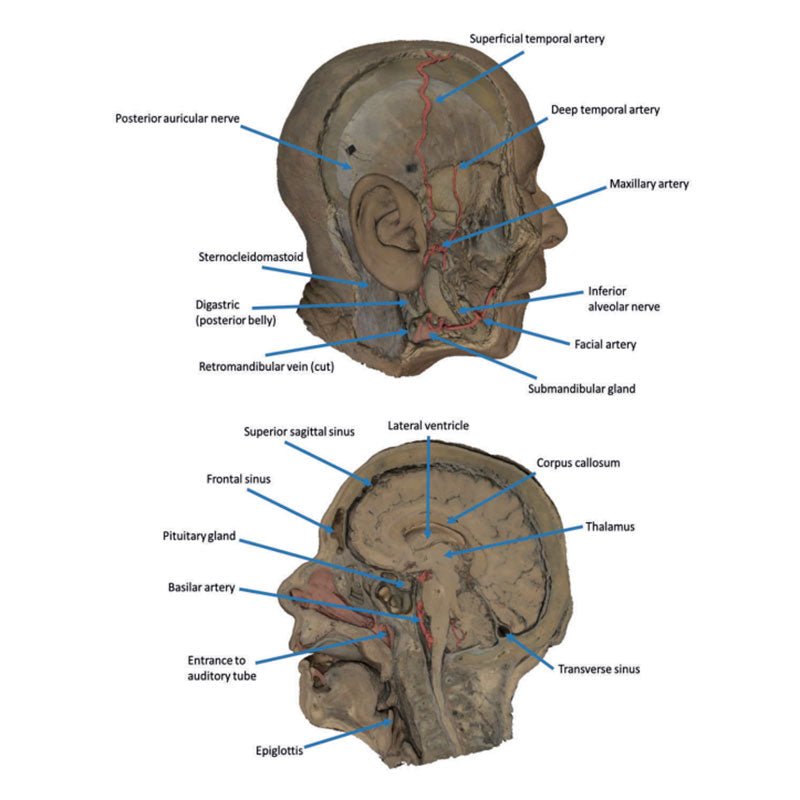

3D Printed Sagittal Section of Head with Infratemporal Fossa Dissection

This 3D model provides a combined midsagittal section through the head and

superior neck coupled with a deep dissection into the infratemporal fossa

region and superficial dissection of the scalp.

In the preserved midsagittal section there is preservation of the endocranial

contents, the nasal and oral cavities, and the pharynx to the level of the

laryngeal cartilages. The nasal cavity is preserved nearly intact, except for a

small window excised into the middle nasal concha to expose the ethmoid

air cells. A very large sphenoid sinus exists in the individual just superior

to the torus of the auditory tube in the nasopharynx. The oral cavity and

laryngopharynx are undissected, with the larynx only preserve just distal to the

level of the arytenoid cartilages and not including a clear set of vocal folds.

Within the endocranial cavity, the sectioned brain is slightly off the midagittal

plane, such that neither the superior sagittal sinus nor the third ventricle are

clearly defined - but the lateral ventricle is open and part of the fourth ventricle

is preserved between the pons and cerebellum. The gyri and sulci of the

cerebrum are not well separated, but the cingulate gyrus and corpus callosum

can be separated. Cross-sectioned views of the optic tract, pituitary gland,

superior and inferior colliculi, superior cerebellar peduncle, and transition

between the medulla oblongata and spinal cord are all visible. The tentorium

cerebelli and confluence/transverse sinus is positioned between the

cerebellar hemisphere and occipital lobe. Small portions of the posterior

inferior cerebellar artery, vertebral arteries, basilar artery, and posterior

cerebral and anterior cerebral arteries are visible in section.

On the opposing side of the model, a superficial and deep dissection has

opened a large window into the anatomy of the lateral scalp and infratemporal

fossa. Across the scalp there is a well preserved posterior auricular nerve

and superficial temporal artery highlighted on the superficial surface of the

temporalis muscle. Anteriorly, the temporalis has been dissected to expose

the deep temporal arteries arising from across the maxillary artery.

The deep level of dissection has exposed parts of the infratemporal fossa

(through partial removal of the mandibular ramus and corpus) and dissection

of retromandibular tissues. At the inferior margin of the dissection window,

the cut edge of the retromandibular vein lies adjacent to the submandibular

gland and the ascending path of the facial artery as it cross towards to angle

of the mouth. Just superior to the cut retromandibular vein is the posterior

belly of the digastric muscle, overlying a small exposure of the deeper

internal jugular vein.

Just posterior to the retained ascending ramus of the mandible are the

external carotid artery and the occipital artery (running in parallel prior

to passing posteriorly). Tracing the external carotid artery superiorly, the

posterior auricular artery, superficial temporal artery, and maxillary artery are

all visible. The maxillary artery passes deep to the lateral pterygoid muscle

and into the infratemporal fossa, reappearing superior to the lateral pterygoid

as it passes into the pterygomaxillary fissure. Along its course, it gives rise

to the posterior deep temporal artery, the inferior alveolar artery (which is

exposed in the dissected mandibular corpus), the anterior deep temporal

artery, and the posterior superior alveolar artery. Finally, the inferior alveolar

nerve can be seen coursing within the opened mandibular corpus, and the

lingual nerve resting on the medial pterygoid. The buccinator muscle is also

retained, with the distal part of the parotid duct preserved as it enters the

muscle towards the oral mucosa